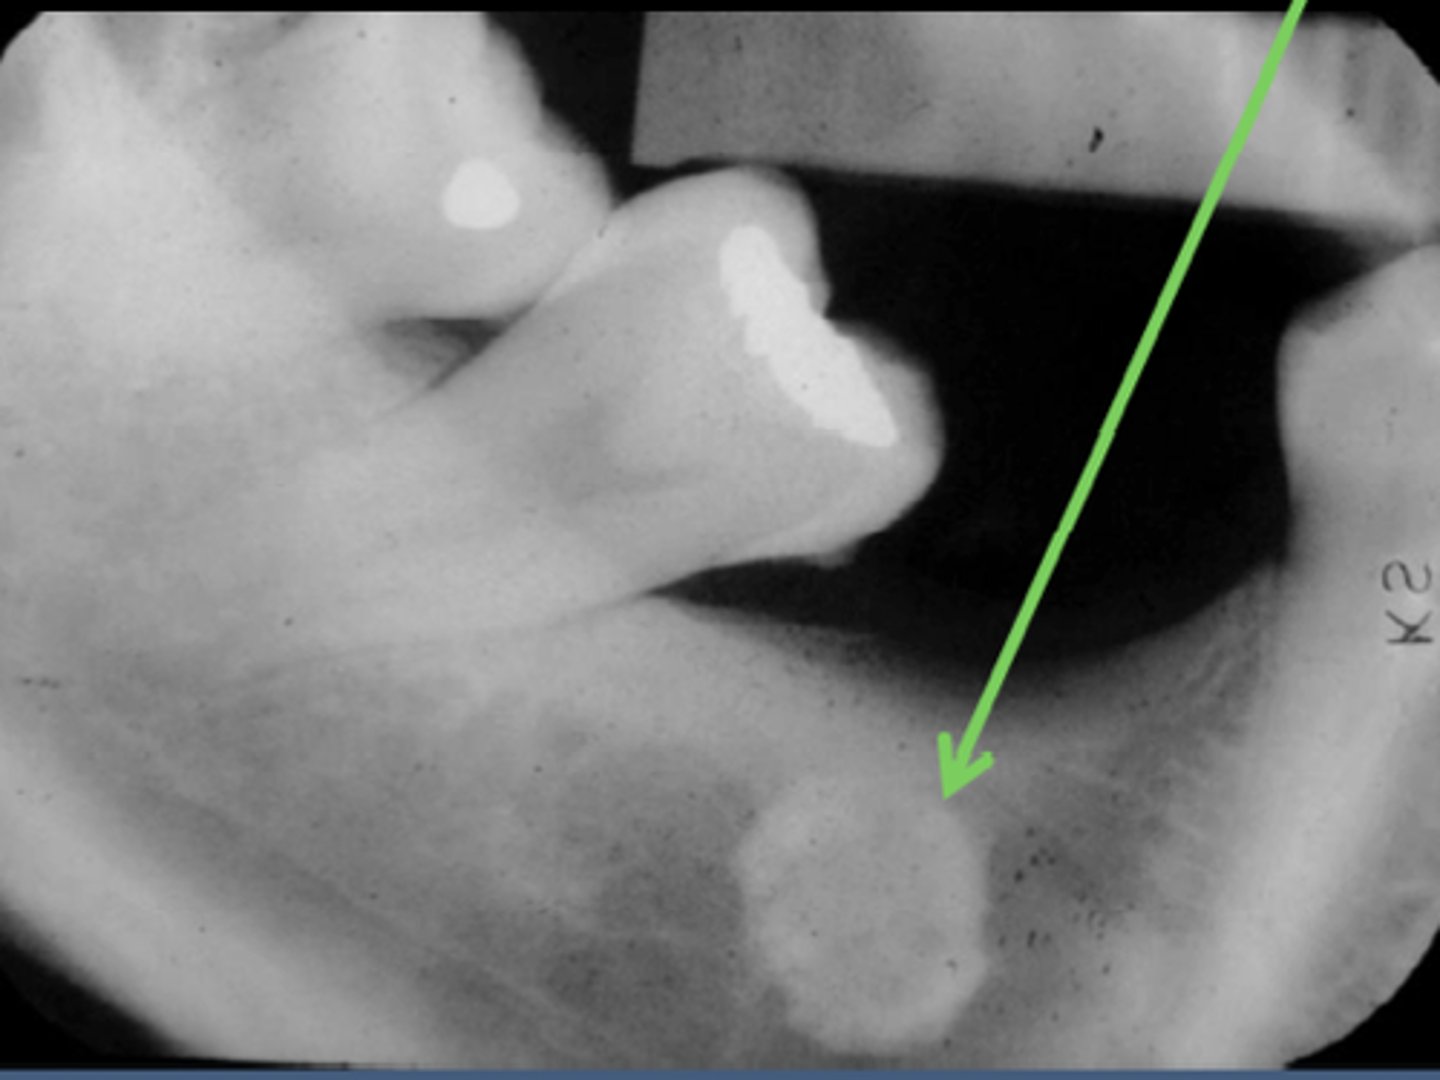

What are the radiographic features of ameloblastomas?

⢠unilocular radiolucency (early lesions)

⢠multilocular radiolucency (honeycomb/soap bubble) (large lesions)

⢠cortical thinning/bone expansion

⢠resorption of adjacent tooth roots + tooth displacement